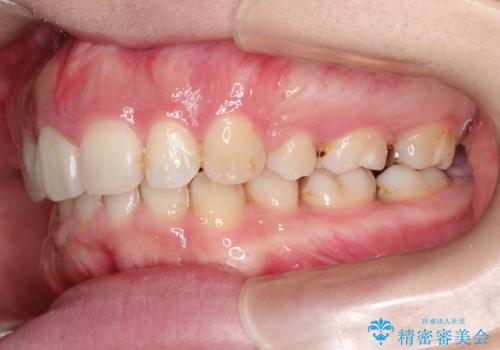

- 歯並びがガタガタなのと、口が閉じずらいのを主訴に来院されました。

上下左右の歯を1本ずつ、合計4本抜歯して、ワイヤー矯正を行うこととなりました。

右上の歯は、歯並び的には前から4番目の歯を抜歯したかったのですが、5番目の歯がすでに治療してある歯でしたのでこちらの歯を抜歯しました。

これにより少し治療期間が延びてしまいましたが、健康な歯を残すことができました。

口元もすっきりとすることがで、口も自然に閉じるようになりました。